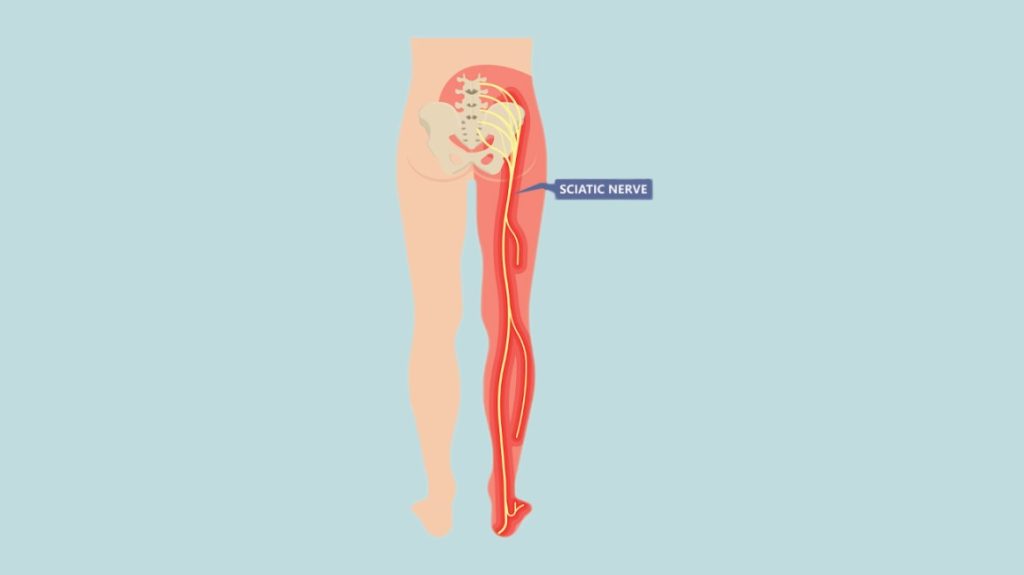

Download Sciatic nerve pain pictures